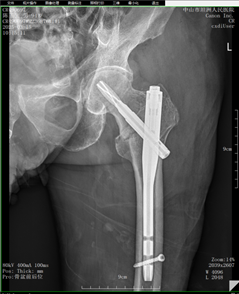

术后DR

该手术切口长约4.0cm,术程50分钟,术中出血仅30ml,十分顺利。

因陈爷爷长期贫血,并患高血压病、糖尿病20余年。骨科邀请麻醉科、消化内科等进行多学科会诊讨论,并为其制定最优化的手术治疗方案——腰硬联合麻下行左股骨粗隆间骨折闭合复位近端防旋髓内钉内固定术。

经过手术,患者恢复良好,患者生活自理能力显著提高。